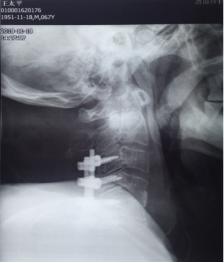

术 前

来市中心医院后,患者四肢肌力上肢1-2级,下肢1级。双下肢腱反射未引出。自胸骨柄以远躯干部位感觉减退。入院后给以各项常规检查,血常规显示白细胞计数12.54×109/L,中性粒细胞绝对值10.85×109/L,,中性粒细胞百分比86.5%,血沉22mm/h,超敏C反应蛋白69.4mg/L。空腹血糖13.88mmol/L。颈椎核磁检查显示颈4/5椎间隙狭小,颈4.5.6椎体T1像低密度,椎体前缘出现炎性浓集。入院初步诊断:颈椎体感染,合并椎间隙脓肿形成,四肢不软瘫,糖尿病II型。在治疗早期即给以广谱抗生素头孢哌酮舒巴坦钠静滴.3.0g,q8h;并口服莫西沙星片,0.4g,qd,使用阿卡波糖控制血糖。再次完善相关检查。全身放射性同位素骨扫描未见肿瘤表象。结核TB淋巴细胞斑点试验阴性,布氏杆菌滴度测定阴性。经治疗,患者体温平稳,血沉,超敏C反应蛋白水平下降明显。后期再次复查颈椎核磁,发现颈椎椎体4.5前缘形成更大的积液表现,椎管内也有形成。随后在B超定位下行颈前肿物穿刺抽吸术,抽出含血浑浊液2ml,分泌物抗酸染色阴性,常规染色图片发现多量的阳性球菌,细菌培养3未见细菌生长。

11月13日行手术治疗,后前路联合手术。先行颈后路切开,颈3-6椎体侧块螺钉固定,再行前路颈4.5间盘以及颈前脓液清理,椎间隙植骨融合术。术中见颈4.5椎间隙前缘被一直径1.5㎝肿物包裹,打开后,可见其内少许米汤样脓性液,肿块壁为脓性物。间盘内充填相同物,上、下缘软骨板漂浮,翘起,上下椎体相邻面骨质酥脆,同时后缘有大量不良增生物,骨钩分离后,可见自颈5椎体后缘,流出同样的米汤样脓液。彻底清理脓性液,充分刮除椎体不良骨质。大量生理盐水冲洗,取三面皮质髂骨块置于椎间隙,敲紧。术后前侧放引流管于脓腔间隙。术后留置3.5天。术中留取的脓液细菌培养仍为阴性,刮出的椎间盘及囊壁病检结果显示为化脓性炎表现。术后继续抗生素治疗,患者体温正常,四肢肌力改善明显,下肢肌力术后第2天恢复至2级。上肢肌力4级弱。躯干部位感觉平面下降至乳头以远,大小便功能改善不明显。